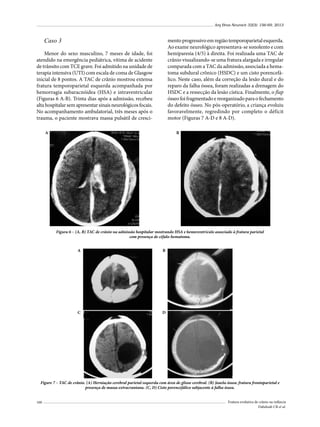

colaboração do paciente.

Existem algumas “armadilhas” quanto ao diagnóstico de lesão de nervos cranianos; por exemplo, a perda de olfação pode ocorrer por simples

obstrução nasal, e não lesão própria em nervo

olfatório; o bloqueio do canal auditivo externo ou

a lesão da orelha média podem causar diminuição

da acuidade auditiva sem lesão do oitavo nervo.

As lesões traumáticas podem decorrer de forças

de cisalhamento, aceleração e desaceleração, lesões

penetrantes, traumas diretos com fraturas cranianas e como sequelas de procedimentos cirúrgicos.

Os objetivos deste trabalho foram: documentar

a incidência de lesões do nervo olfatório associadas a TCE; correlacionar as lesões com achados

radiológicos (fraturas, afundamentos e lesões

intracranianas) e etiologia traumática (atropelamentos, acidentes automobilísticos etc.); relatar

a distribuição de frequência das lesões isoladas

e múltiplas associadas à lesão do nervo olfatório,

identificando quais as associações de lesões são

mais frequentes; correlacionar a incidência de

fístula liquórica com a presença de lesão de nervo

olfatório e revisar a literatura.

Casuística e método